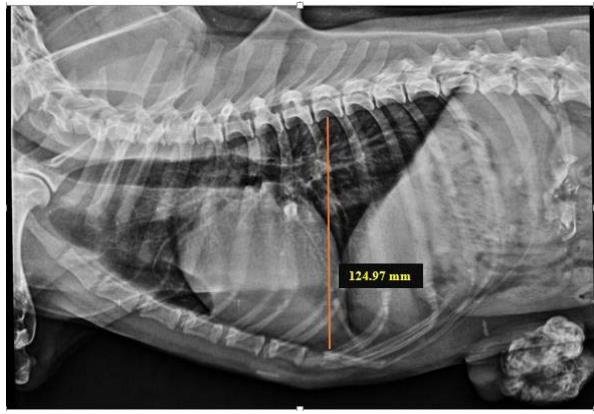

Tracheal Diameter: Tracheal Inlet (TD: TI) ratio was calculated by recording the diameter of the trachea at the level of the thoracic inlet and the inner diameter of the thoracic inlet (Fig 1). Cardiothoracic ratios (CTR) were calculated by dividing the largest width of the thorax by chest depth on radiographs (Fig 3). On a dorsoventral/ventrodorsal radiograph, the width of the thorax was measured as the distance between the medial borders of the eight ribs (Fig 4). The depth was assessed on the right lateral radiographic view from the dorsal margin of the xiphoid process to the ventral margin of the vertebral body, with the electronic calipers aligned perpendicular to the vertebral column. The Vertebral heart score was calculated according to Buchanan and Bucheler, 1995 (Fig 2).

Group I animals had a Cardio-thoracic ratio ranging from 0.73- 1.03, and Group II had a cardio-thoracic ratio ranging from 0.69-1.12. All the animals had CTR values in the normal range irrespective of type of the neoplasm.

Fig. 3: Skiagram showing measurement of chest depth on right lateral view for assessment of the cardiothoracic ratio

Cardiothoracic ratio, CTR = Largest width of the thorax/Chest Depth = 0.89